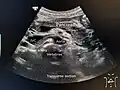

A normal pancreas on ultrasound.

Identifying pancreas on abdominal ultrasonography when it is partly obscured by bowel gas.